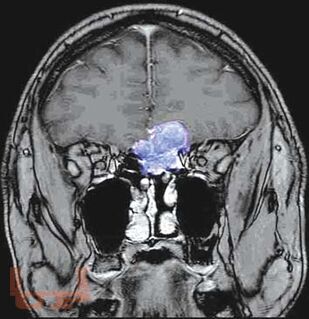

Первичные опухоли головного мозга

Кратко изложены этиология, особенности эпидемиологии, патогенеза, классификация и основные клинические проявления первичных опухолей головного мозга, современные принципы клиники, диагностики и оказания госпитальной помощи больным с данной патологией. Представлены алгоритмы обследования и лечения больных с наиболее часто встречающимися опухолями в зависимости от стадии течения патологического процесса.